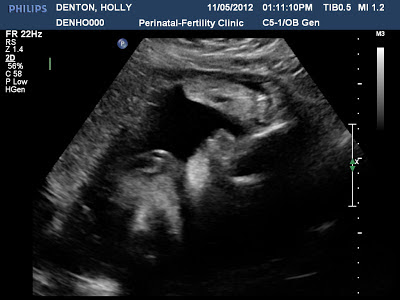

Here are some pictures of today!

| 30 weeks 5 days! |

| Looks a little weird but that is her mouth opening LOL |

| This is a FUNNY picture of her face profile and then at the top right of the corner you see her foot and then her fingers are wrapped around her toes playing with her little foot LOL |